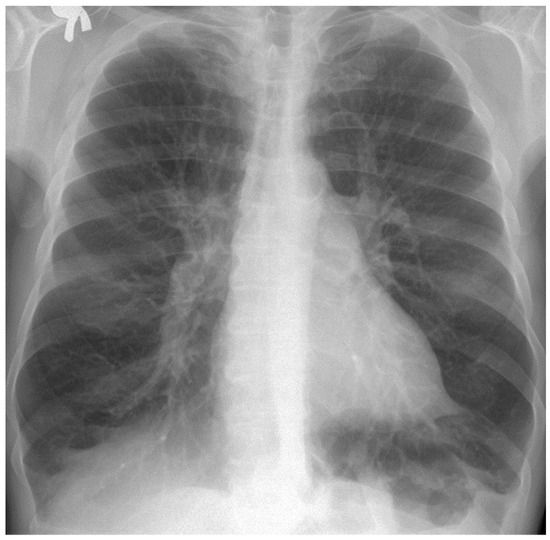

In this subsection, we present and discuss the pulmonary CT scan of healthy lungs, which were not affected by the presence of SARS-CoV-2.

The chest radiograph of healthy lungs on which the fractal analysis was performed is shown in Figure 29a. Aside from the high-quality imaging provided by CT procedures (Figure 29a,b), the picture evaluation assured quantitative information regarding various structural features, such as the fractal dimension and lacunarity.

Figure 30 shows the 2D box-counting algorithm with the local fractal dimension calculation for the healthy-lung CT image. Figure 31 displays the 3D graphical representation of the voxels present in the CT lung image of healthy patient. Table 7 presents the calculated values for the fractal dimension and the lacunarity of the CT image evaluations for the healthy patient.

Table 7 shows the known fractal indicators, such as the fractal dimension of the CT image of the left lung, dHL = 1.6410 ± 0.3577, and lacunarity Λ = 0.0475; and the fractal dimension of the right lung, dHR = 1.6318 ± 0.3598, and lacunarity, Λ = 0.0486.

Figure 29. (a) Healthy lung image, (b) binary version, (c) mask for the left lung, (d) mask for the right lung.